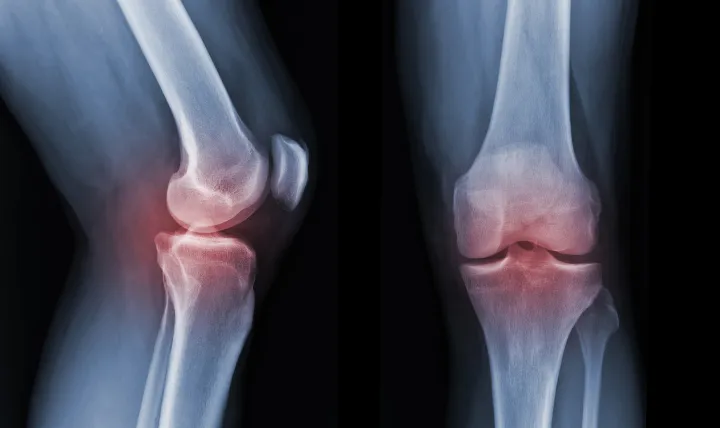

ジャンプやダッシュ、ボールを蹴る動作などで太ももの前の筋肉(大腿四頭筋)が繰り返し強く収縮すると、膝のお皿の下にある骨の付着部が引っ張られます。

成長期のお子さんはこの部分の骨がまだ柔らかい軟骨であるため、過度な負担がかかることで炎症が起き、痛みや腫れを引き起こすのです。

サイン②:膝下(すねの上)の骨がポコッと出っ張ってくる

炎症が続くと、常に引っ張られている膝下の骨の付着部が、徐々に隆起してきます。

痛くない方の脚と比べてみると、痛い方の膝下だけがポコッと出っ張っているのが分かるはずです。

この骨の隆起は、オスグッド病の最も

特徴的なサインの一つで、炎症が治まった後も、大人になっても残ることがあります。